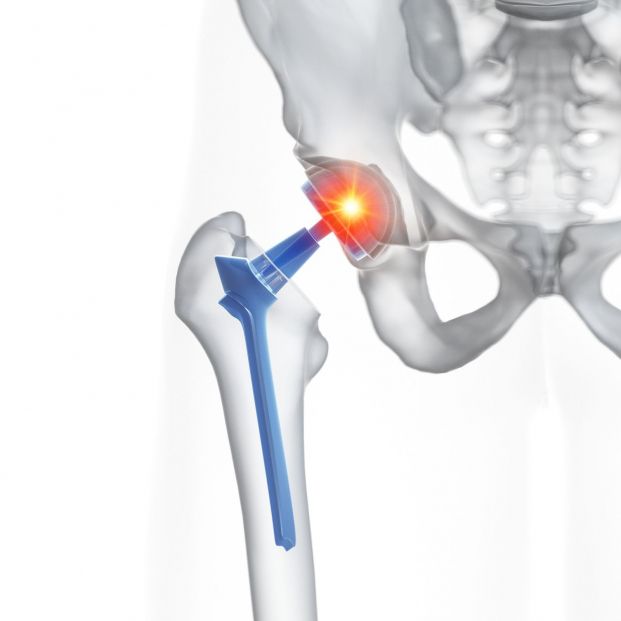

La anestesia epidural y raquídea se emplea en intervenciones relacionadas con fracturas de cadera

Las dos pueden usarse para procedimientos relacionados con los genitales o las vías urinarias, como es el caso de la resección de la próstata, por ejemplo. También para trastornos de la parte inferior del cuerpo como pueden ser las varices. Asimismo, en algunos casos las fracturas de cadera se operan con anestesia raquídea.

La epidural se utiliza también además de en los partos, para cirugías relacionadas con la pelvis como por ejemplo en la del suelo pélvico.